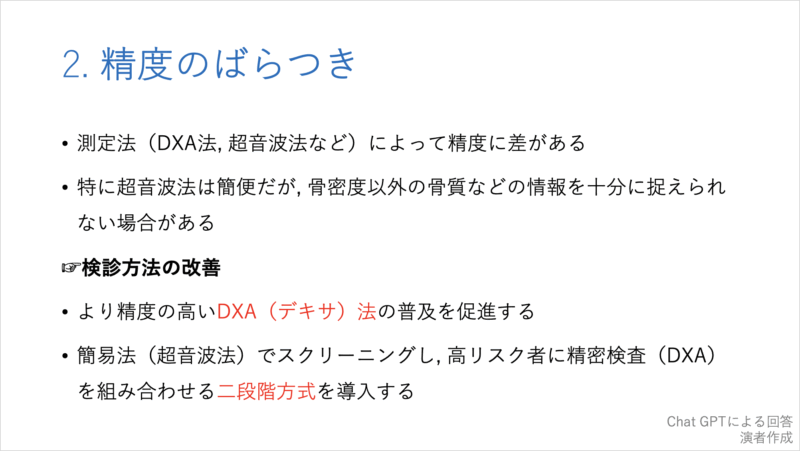

20時過ぎから, 私がclosing remarksとして, 10分で骨粗鬆症検診の問題点とその対策, および各県庁所在地での現状について, チャットGPTからの回答をからめてお話ししました. 途中で, 自分の大腿骨頚部骨折のことも取り上げました.